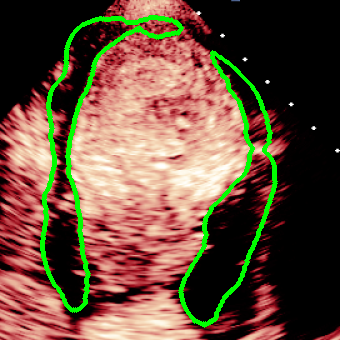

For variations caused by low quality images such as those of low resolution or significant artifacts, however, the unique ground truth may not be available. Take the myocardial segmentation task of Myocardial Contrast Echocardiography (MCE) as an example. An inter-observer experiment was conducted among five experienced cardiologists, and Fig. 1(a)(b) visualize the annotations of two images from three of these cardiologists. It can be seen that the labels by different cardiologists vary significantly, especially in locations where the intensity information of myocardium is very similar to the background. Table 1 shows the average Dice of the annotation of each cardiologist, using one of the others’ as the ground truth, over 180 images. We can observe that none of the Dice is above 0.9, some even under 0.8, confirming significant variations among the annotations. In this case, as the variations are caused by the image quality, even these cardiologists cannot tell which annotation is better than others, and a majority vote for ground truth would not make sense sometimes as can be seen in Fig. 1(c)(d). For this reason, we cannot obtain a unique ground truth in the evaluation process and the traditional metrics such as Dice and IoU cannot be used.